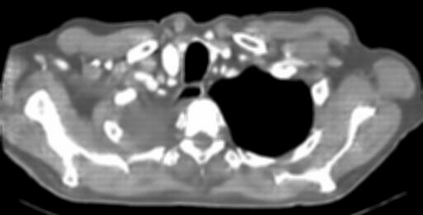

Due to the constraints of the imaging device and high cost in operation time, computer tomography (CT) scans are usually acquired with low intra-slice resolution. Improving the intra-slice resolution is beneficial to the disease diagnosis for both human experts and computer-aided systems. To this end, this paper builds a novel medical slice synthesis to increase the between-slice resolution. Considering that the ground-truth intermediate medical slices are always absent in clinical practice, we introduce the incremental cross-view mutual distillation strategy to accomplish this task in the self-supervised learning manner. Specifically, we model this problem from three different views: slice-wise interpolation from axial view and pixel-wise interpolation from coronal and sagittal views. Under this circumstance, the models learned from different views can distill valuable knowledge to guide the learning processes of each other. We can repeat this process to make the models synthesize intermediate slice data with increasing inter-slice resolution. To demonstrate the effectiveness of the proposed approach, we conduct comprehensive experiments on a large-scale CT dataset. Quantitative and qualitative comparison results show that our method outperforms state-of-the-art algorithms by clear margins.